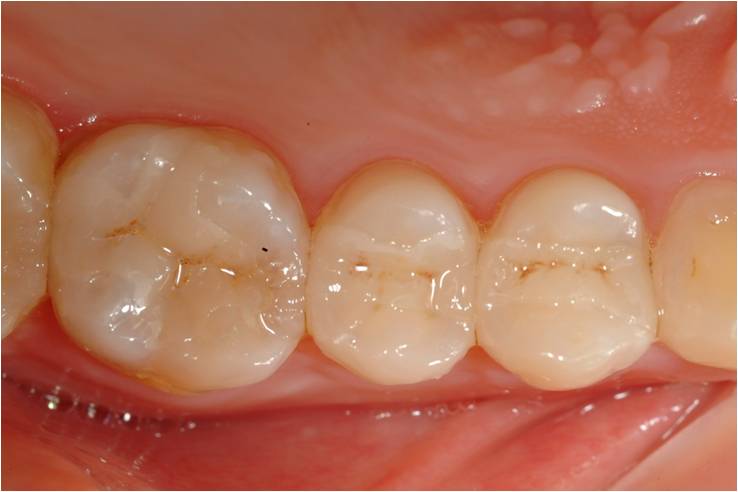

黏著後狀態

術前、術後比較